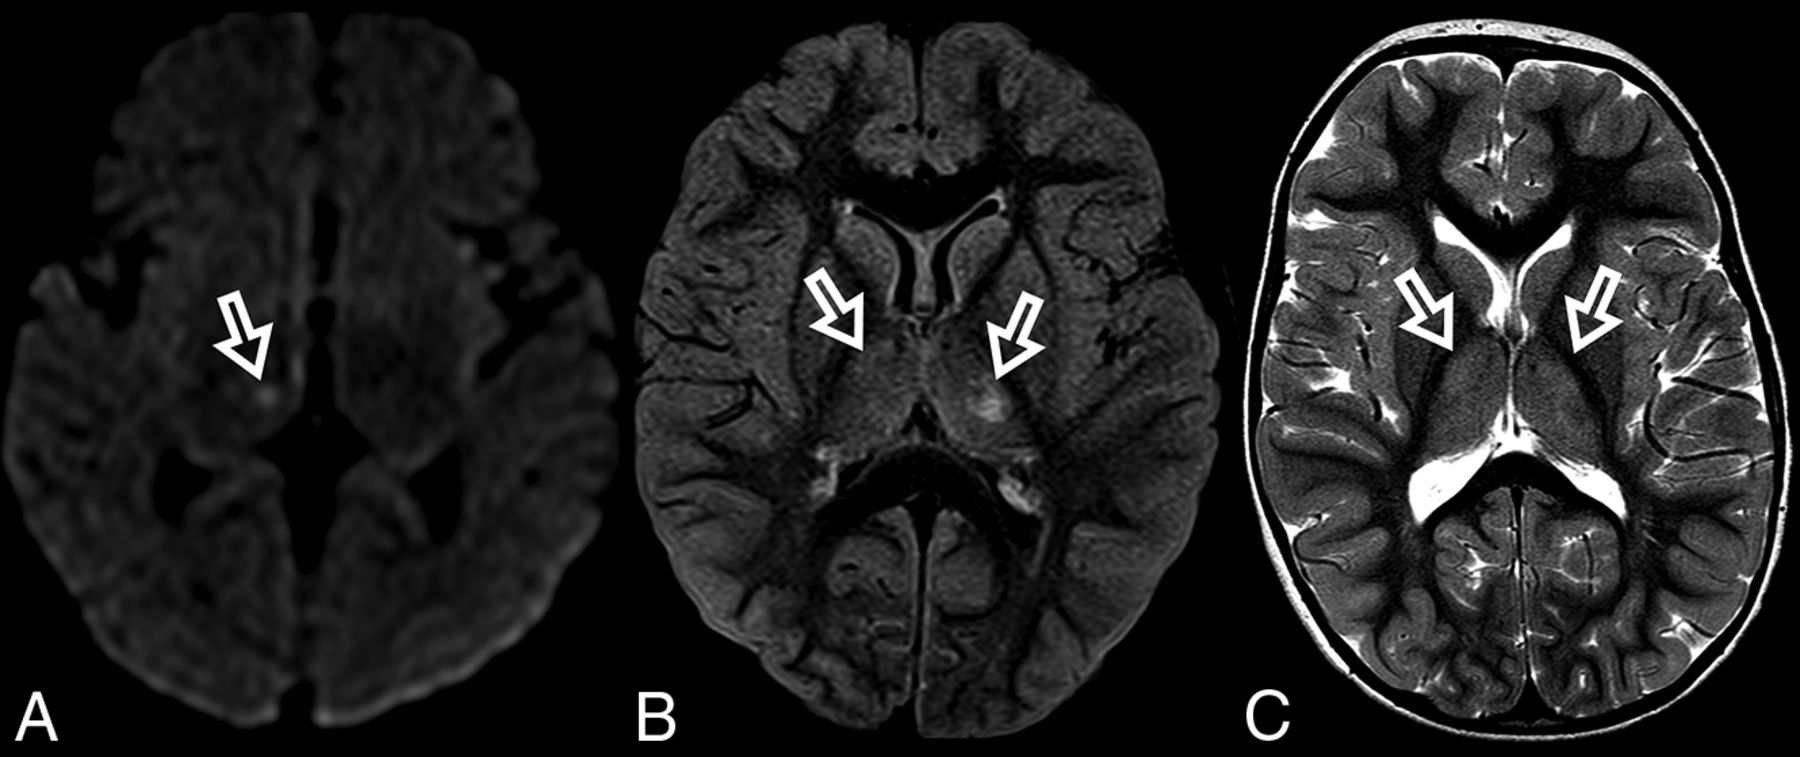

At diagnosis, brain MR imaging findings were abnormal in most patients (n = 12, 92%). The most common brain MR imaging findings were unilateral or bilateral perirolandic signal changes (n = 7, 54%) (Fig 1) and unilateral or bilateral thalamic signal changes (n = 10, 77%) (Fig 2). Perirolandic signal abnormalities were unilateral in most cases (n = 5, 71%) and were more frequently seen only affecting the precentral or both the pre- and postcentral gyri. Half of the thalamic changes were unilateral (n = 5, 50%). Simultaneous perirolandic and thalamic signal changes occurred in 6 patients (n = 6, 46%). An association of EPC (clinically/EEG) and perirolandic signal changes was present in 6 patients (n = 6, 75%), and an association of EPC (clinically/EEG) and thalamic signal changes, in 7 patients (n = 7, 87.5%). Two patients with EPC (clinically/EEG) did not present with perirolandic signal abnormalities. The findings positive for lesions overall were on the DWI of 10 patients (n = 10, 83%), on the T2WI of 9 patients (n = 9, 75%), and on FLAIR of 7 patients (n = 7, 58%). In 4 patients, DWI was the only sequence with abnormal findings. The occipital lobe was affected in the early brain MR imaging in 2 patients (n = 2, 15%). Signal changes in other brain regions were found in 5 patients (n = 5, 42%), involving multiple regions, namely the cerebral white matter, insula, putamen, caudate nucleus, fornix, cerebellar vermis, and also the frontal and occipital lobes. One patient did not present with either perirolandic or thalamic changes but instead presented with a diffuse pattern similar to that of leukoencephalopathy, with restricted diffusion in the white matter and white matter tracts (Fig 3). Three patients had an abnormally high lactate peak on MR spectroscopy. None of our patients had ASL or other perfusion-weighted imaging at the time of diagnosis. T1 and T2* imaging and SWI had negative findings at the time of diagnosis.

ADC map images of a 7-month-year old male with POLG-related disorder, demonstrating a diffuse pattern of leukoencephalopathy with restricted diffusion of the periventricular white matter of the bilateral temporal lobes in A, the occipital lobes in B, and also of the bilateral fornix in C and corpus callosum in D.